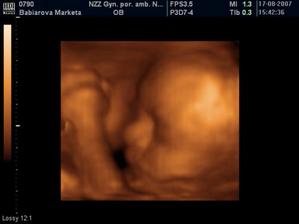

Naše bábätko

Začala sa moja cesta vývinu a mal by som prísť na svet 1.12.07.